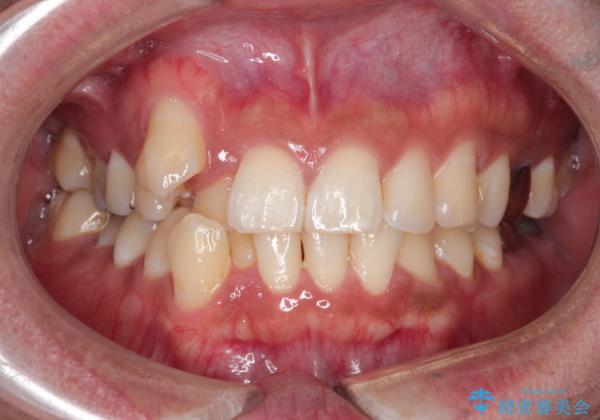

【ワイヤー矯正】八重歯と下の歯の凸凹を治したい

- 主訴:右上の八重歯と、下の歯の凸凹を治したい

右側2級、左側1関係だったため、右側上下第一小臼歯を抜歯し、ワイヤー矯正を行いました。

期間:2年6カ月